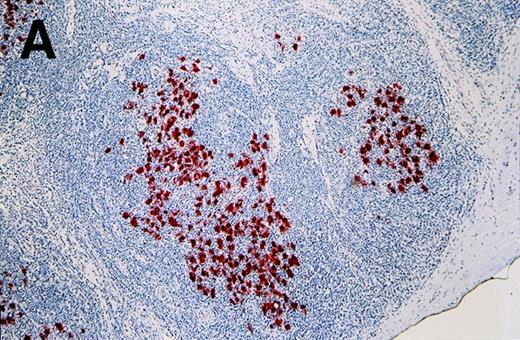

Antibody 57B stained 11 of 53 HD samples (21%), whereas no sample was stained by an isotype-matched control antibody. The positive samples included 1 of 3 HD type I, 8 of 34 HD type II, 2 of 14 HD type III, and 0 of 2 HD type IV. Representative results from patients HD3 and HD4 are shown in Figure 2. Positive cells are distributed in the different nodules (Figure 2A). At higher magnification, the staining is clearly observed in Reed-Sternberg cells (Figure 2B and 2C). Even though a weak background staining is present around some Reed-Sternberg cells, the reactive small lymphocytes and histiocytes are not stained.

Labeling of Reed-Sternberg cells with anti–MAGE-A4 MAb 57B in nodular sclerosing lymph nodes.

Patients include HD3 (A and B) and HD4 (C) at low (A), high (B) and intermediate (C) magnification. (B) and (C) correspond to MAGE-A4expression in HD3. Formalin-fixed sections were deparaffinized, heated in a citrate buffer, and incubated with MAb 57B. The antibody was detected with biotinylated secondary antibodies and avidin-coupled alkaline phosphatase. The chromogenic substrate was New Fuschin, and hematoxylin was used to counterstain the tissue.